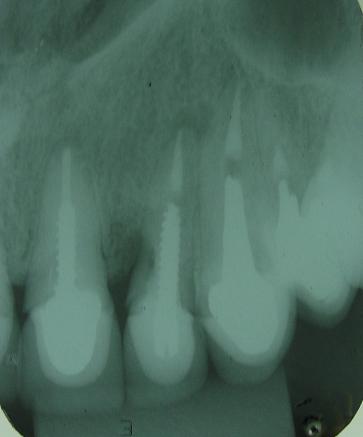

Radiografia da raiz fraturada